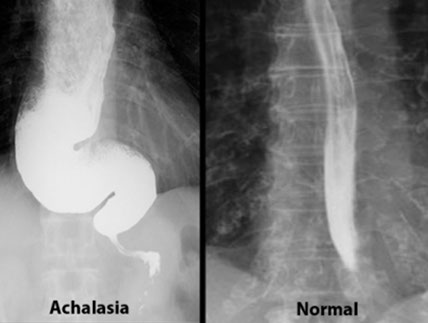

Achalasia

from Greek: A- (not); chalao (loosen / relax)

MCC Neuromuscular disorder of esophagus

inc LES tone from impaired sm muscle relaxation

Primary achalasia 2/2 degeneration of inhibitory neurons in distal esophagus

Secondary achalasia can be in Chagas, where LES fails to relax b/c destruction of myenteric (Auerbach's) plexus.

- inflam. of esophageal myenteric plexus is pathomneumonic

- damage to inhibitory (NO synthase producing) neurons

- can also be seen in DM, malig, amyloidosis, sarcoidosis, polio, surgical ablation of nerves, Down syndrome, Allgrove syndrome

Triad:

1)incomplete LES relaxation,

2) inc LES tone

3) esophageal aperistalsis

High LES opening pressure + uncoordinated peristalsis --> progressive dysphagia to solids AND liquids

- dysphagia limited to solids indicates an obstructive lesion

Primary achalasia 2/2 ganglion cell degen (inhibitory neuron degeneration, thus inc tone)

May be caused by Chaga's dz./ Scleroderma (CREST syndrome), diabetic neuropathy, or amyloidosis

Generally, worsening dysphagia to solids and liquids indicates motility disorders --> achalasia, MG, stroke, CREST syndrome

- Dysphagia limited to solids indicates an obstructive lesion (ie an esophageal web / cancer)

Dx: Manometry studies. Barium swallow shows "bird's beak" (stenosis of distal esophagus).

- manometry findings: 1) Aperistalsis; 2) dec LES relaxation after swallowing; 3) inc LES resting tone

Tx: 1) Pneumatic balloon dilation (may cause rupture)

2) Botulinum toxin injection to LES

3) Esophagotomy

Px: small (1/20) risk of esophageal SCC

- thus pt should get bx more frequently (annually?)